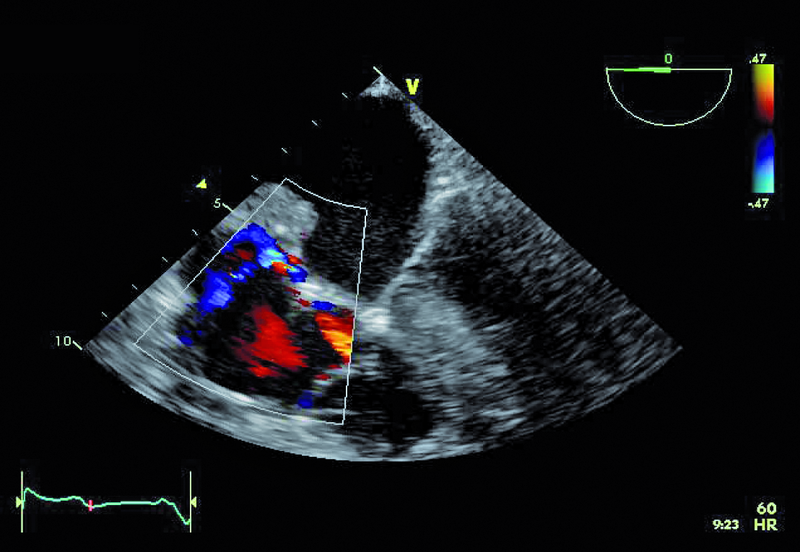

Kobieta, lat 55. Jakie patologie można rozpoznać na zamieszczonych rycinach?

1. Guz przegrody międzyprzedsionkowej (ryc. 1-3).

2. Mały ubytek przegrody międzyprzedsionkowej z przeciekiem lewo-prawym (ryc. 1-3).

4. Istotny przerost przegrody międzykomorowej (ryc. 1, 2, 5).